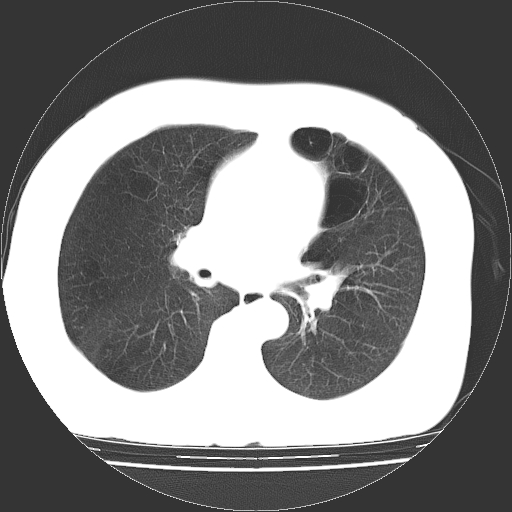

标题: CT13141:女,70岁,咳嗽、胸闷半个月。 [打印本页]

标题: CT13141:女,70岁,咳嗽、胸闷半个月。

女,70岁,咳嗽、胸闷半个月。纵隔窗未见异常,未上传。

1.小叶中心型肺气肿。

2.左肺下舌段感染性病变。

肺大疱的壁甚薄,由肺泡的扁平上皮细胞组成,也可能仅为纤维性膜。可与多种肺气肿并存,常见于间隔旁侧或细叶旁肺气肿,可伴有碳末沉着,如煤矿工人尘肺,或不伴有碳末沉着,如瘢痕组织肺气肿。根据病理形态将肺大疱分为三种类型。

ⅰ型:狭颈肺大疱。突出于肺表面,并有一狭带与肺相连。因为支气管瘢痕组织形成的活瓣性阻塞,肺大疱体积增大系由于肺泡侧支通气和气体滞留。ⅰ型肺大疱壁薄,常由胸膜和结缔组织形成,多发生于中叶或舌叶,也常见于肺上叶,可能由于该部位胸腔负压大,常规胸片即可发现肺大疱的存在。

ⅱ型:宽基底部表浅肺大疱。位于肺表层,在脏层胸膜与气肿性肺组织之间。肺大疱腔内可见结缔组织间隔,但它不构成肺大疱的壁,可见于肺的任何部位。

ⅲ型:宽基底部深位肺大疱。结构与ⅱ型相似,但部位较深,周围均为气肿性肺组织,肺大疱可伸展至肺门,可见于任何肺叶。

当肺大疱体积增大时,周围肺组织受压迫并引起肺脏移位。受压肺组织在x线胸片上,表现为肺大疱周围密度增高阴影。以上三型均见于慢性支气管炎。小叶中心型肺气肿不并发肺大疱。下叶肺大疱常见于有并发症的煤矿工人尘肺和融合性矽肺。